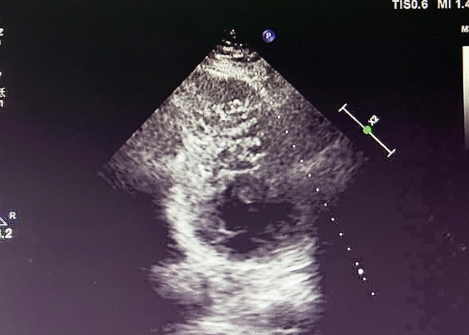

入院后,患者接受超聲心動(dòng)圖檢查,結(jié)果顯示左心室心肌呈典型 “海綿樣” 改變,可見(jiàn)多發(fā)、粗大的肌小梁和深陷的隱窩,非致密化心肌層與致密化心肌層比值(NC/C)>2.3,完全符合左心室心肌致密化不全(LVNC)的超聲診斷標(biāo)準(zhǔn)。

LVNC 的超聲表現(xiàn)

(1)特征性表現(xiàn)左心室壁明顯增厚,內(nèi)層心肌呈 “網(wǎng)狀” 疏松結(jié)構(gòu),外層致密心肌變薄,血流灌注顯示隱窩內(nèi)血流緩慢,這種情況容易形成血栓。(2)診斷標(biāo)準(zhǔn)(Jenni 標(biāo)準(zhǔn))收縮末期非致密化心肌層與致密層厚度比 > 2,可見(jiàn)深陷的肌小梁間隱窩與心室腔交通。